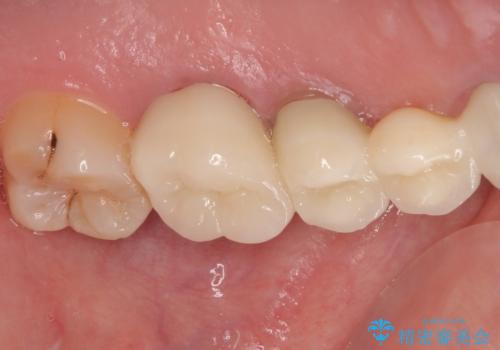

銀歯や欠損が大きいことから、虫歯治療後はオールセラミッククラウンによる補綴治療を行うこととしました。

やはりむし歯は大きく、一部歯髄を切除することとなりましたが、その後は良好な経過をたどっています。